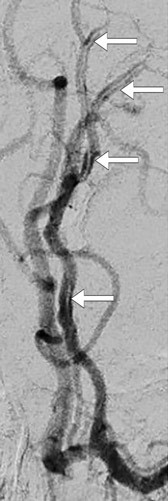

Cerebral MRI the day after admission (pictured left) revealed infarction of the left medial frontal lobe, corresponding to the area supplied by the left anterior cerebral artery, and time-of-flight MR angiography showed thrombosis in the A2 segment of the artery. The patient underwent extensive investigation, but the underlying cause of the infarct could not be determined. After two weeks, conventional cerebral angiography revealed a dissection in the A2 segment of the left anterior cerebral artery (pictured right). A month later she was back in full-time employment, and her NIHSS (National Institute of Health Stroke Scale) and modified Rankin Scale (mRS) scores were both 0.